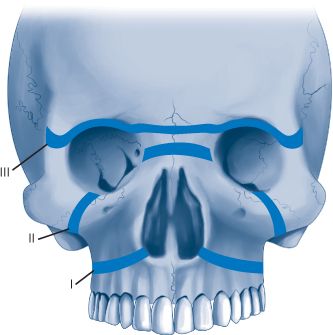

Le Fort I fractures occur transversely across the alveolus, above the level of the teeth apices. In a pure Le Fort I fracture, the palatal vault is mobile while the nasal pyramid and orbital rims are stable. The Le Fort II fracture extends through the nasofrontal buttress, medial wall of the orbit, across the infraorbital rim, and through the gomaticomaxillary articulation. The nasal dorsum, palate, and medial part of the infraorbital rim are mobile. The Le Fort III fracture is also known as craniofacial disjunction. The frontozygomaticomaxillary, frontomaxillary, and frontonasal suture lines are disrupted. The entire face is mobile from the cranium. It is convenient to conceptualize complex midface fractures according to these patterns (Fig. 18-6); however, in reality, fractures reflect a combination of these three types. Also, the fracture pattern may vary between the left and right sides of the midface. (See Schwartz 9th ed., p 487.)

FIG. 18-6. Classic Le Fort fracture patterns.